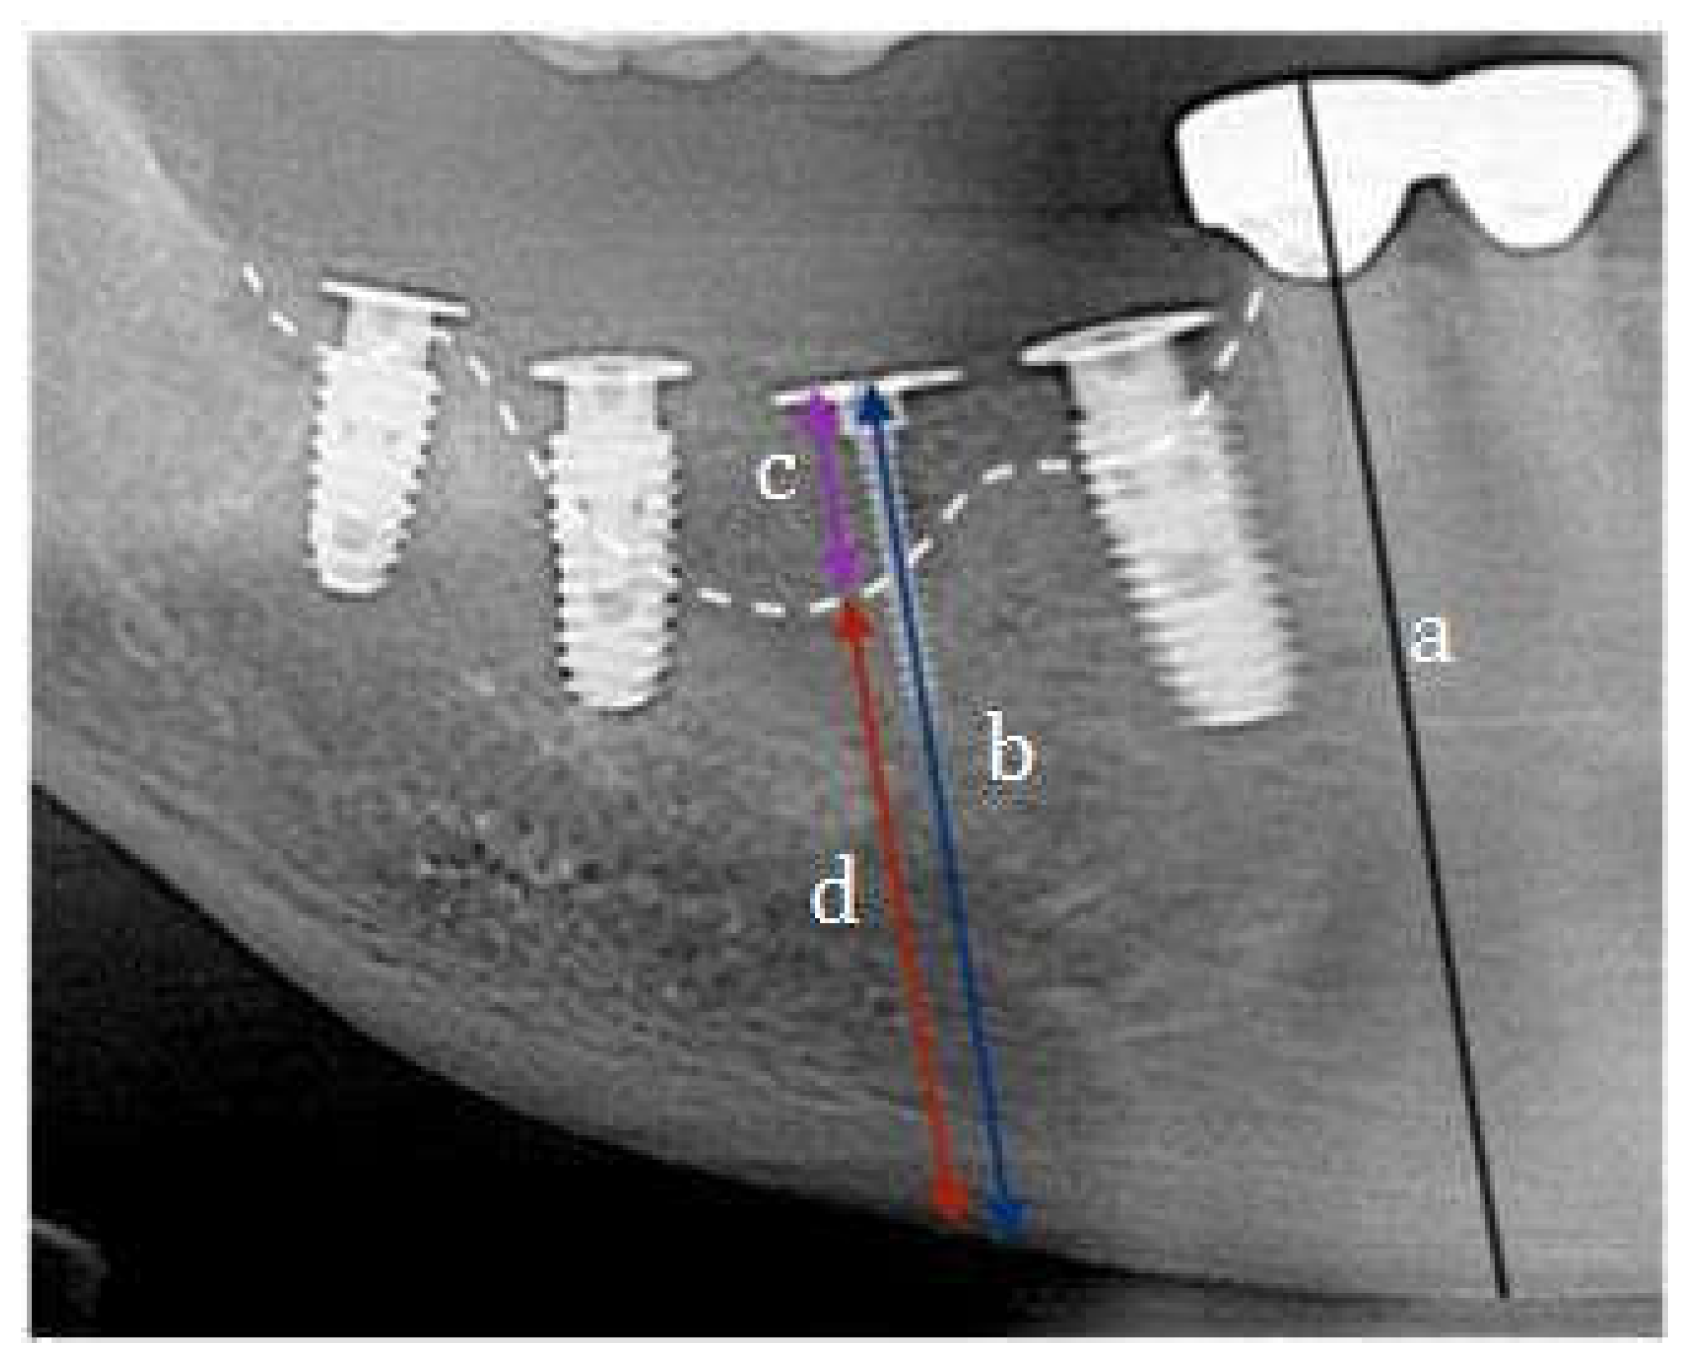

- Woo, R.H.; Kim, H.G.; Kim, G.; Park, W.E.; Sohn, D.S. Simplified 3-dimensional ridge augmentation using a tenting abutment. Adv Dent & Oral Health 2020, 12, 185–205. [Google Scholar]

- Woo, R.H.; Kim, H.G.; Kim, G.; Park, W.; Sohn, D. Simplified 3-Dimensional ridge augmentation using a tenting abutment. Adv Dent Oral Health 2020, 12, 185–205. [Google Scholar]

- Sohn, D.S. Reconstruction of three-dimensional alveolar ridge defects utilizing screws and implant abutments for the tent-pole grafting` techniques. In Tolstunov L, ed. Essential techniques of alveolar bone augmentation in implant dentistry, 2nd ed.; Wiley Blackwell: 2023; 404-418.

- Sohn, D.S.; Lui, A.; Choi, H. Utilization of Tenting Pole Abutments for the Reconstruction of Severely Resorbed Alveolar Bone: Technical Considerations and Case Series Reports. J. Clin. Med. 2024, 13, 1156. [Google Scholar] [CrossRef] [PubMed] [PubMed Central]